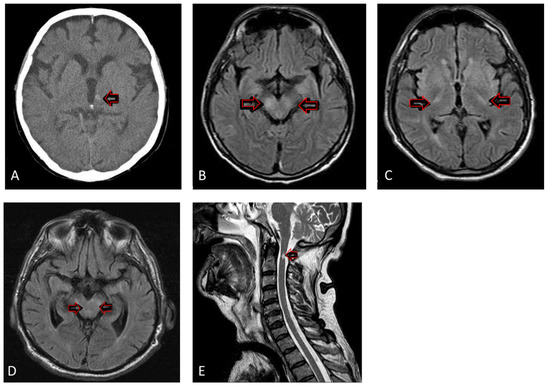

2.4. Neuroimaging and Electroencephalography Results

- Zak, I.T.; Altinok, D.; Merline, J.R.; Chander, S.; Kish, K.K. West Nile virus infection. Am. J. Roentgenol. 2005, 184, 957–961. [Google Scholar] [CrossRef] [PubMed]

- Bailey, C.; Mach, J.; Kataria, S.; Tandon, M.; Lakhani, D.A.; Sriwastava, S. West Nile virus encephalitis: A report of two cases and review of neuroradiological features. Radiol. Case Rep. 2020, 15, 2422–2426. [Google Scholar] [CrossRef] [PubMed]

- Ali, M.; Safriel, Y.; Sohi, J.; Llave, A.; Weathers, S. West Nile virus infection: MR imaging findings in the nervous system. Am. J. Neuroradiol. 2005, 26, 289–297. [Google Scholar]

- DeQuesada, I.; Saindane, A. West Nile virus presenting as flaccid paralysis: Case report and literature review. Radiol. Case Rep. 2012, 7, 705. [Google Scholar] [CrossRef][Green Version]

- Hwang, J.; Ryu, H.S.; Kim, H.; Lee, S.A. The first reported case of West Nile encephalitis in Korea. J. Korean Med. Sci. 2015, 30, 343–345. [Google Scholar] [CrossRef] [PubMed]

- Jeha, L.E.; Sila, C.A.; Lederman, R.J.; Prayson, R.A.; Isada, C.M.; Gordon, S.M. West Nile virus infection: A new acute paralytic illness. Neurology 2003, 61, 55–59. [Google Scholar] [CrossRef] [PubMed]

- Petropoulou, K.A.; Gordon, S.M.; Prayson, R.A.; Ruggierri, P.M. West Nile virus meningoencephalitis: MR imaging findings. Am. J. Neuroradiol. 2005, 26, 1986–1995. [Google Scholar]